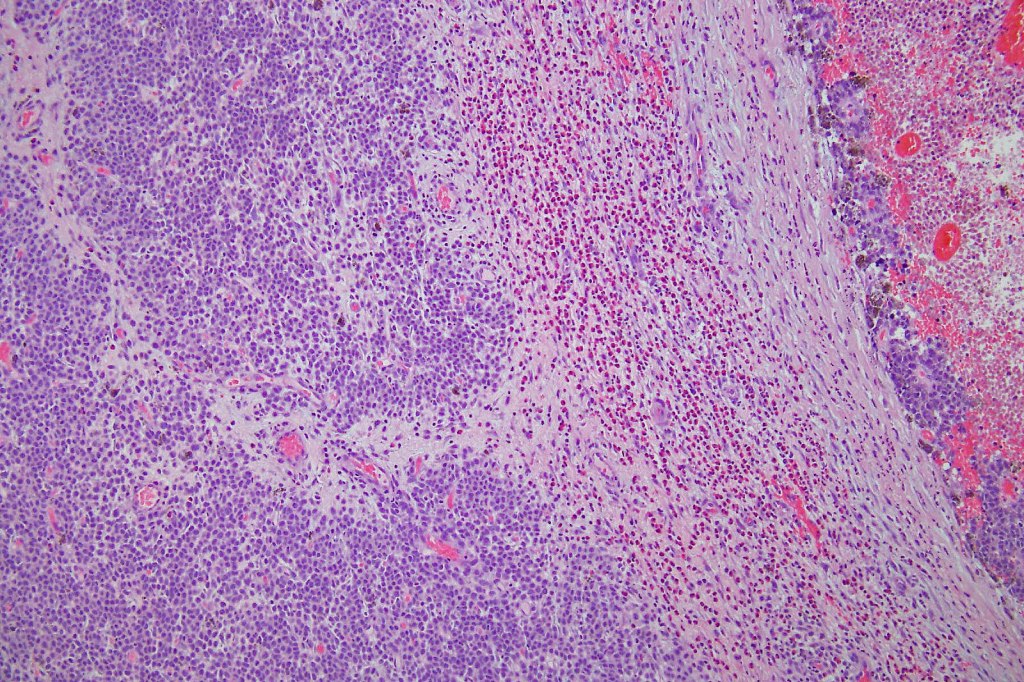

This melanoma arose in a small congenital nevus of the scalp. It metastasized widely. Varying features in different fields.